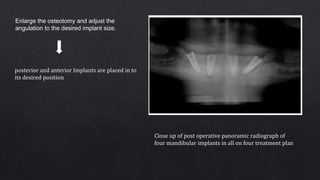

Enlarge the osteotomy and adjust the

angulation to the desired implant size.

posterior and anterior Implants are placed in to

its desired position

Close up of post operative panoramic radiograph of

four mandibular implants in all on four treatment plan